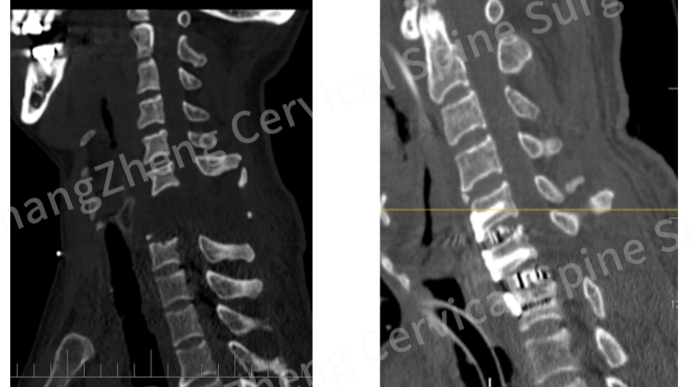

影像学检查的结果令人窒息:颈椎发生了极其罕见的大跨度脱位,严重程度犹如“身首离断”,脊髓严重挫伤,关键神经血管结构撕裂。雪上加霜的是,骨折脱位区域形成的巨大血肿,以及双侧椎动脉因损伤而闭塞,让患者的血压如同失控的过山车,频繁骤降至约50mmHg的危险值,全靠大剂量升压药物在生死边缘勉强维系循环。

无影灯下,医生们踏上的是一条充满未知与凶险的征途。首要威胁悬在头顶:椎动脉大出血。CT造影显示,患者右侧椎动脉断裂,幸被骨折组织和血凝块暂时封堵;左侧椎动脉则被牵拉得“像一根被拉长的细管”,仅存一丝脆弱血流。“椎动脉压力很高,术中一旦血凝块松动,几秒内失血可达1000至2000mL,人可能瞬间就没了。”陈华江深知其险。更令人揪心的是,患者伤情过重,连完善检查都成奢望,“稍一挪动,血压就掉到50mmHg以下”。这意味着手术团队将在未知中“走一步、看一步”。

历经约3小时惊险鏖战,关键突破降临!团队不仅精准复位了完全离断错位的颈椎,更创新性地应用了“卫星钢板”技术。在仅有24至26mm宽的椎体上,他们成功植入双钢板加双融合器,巧妙增加辅助钢板,实现了前路一期的超强稳定。它如同定海神针,为濒临崩溃的颈椎提供了关键的即刻稳定,避免了二次手术的巨大风险。“这一技术应用在此类极端病例中尚属首创。”陈华江介绍。